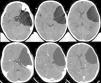

Los quistes aracnoideos son lesiones quísticas malformativas que contienen en su interior un líquido de características similares al líquido cefalorraquídeo. Constituyen alrededor del 1% de todos los procesos ocupantes de espacio a nivel intracraneal y, en los últimos años, su incidencia se ha incrementado ligeramente debido a la mejora en las técnicas de diagnóstico radiológico.

Aunque la mayoría de los quistes aracnoideos se sitúan en la cavidad craneal, especialmente en la región de la cisura de Silvio, un menor número de casos pueden localizarse a nivel espinal.